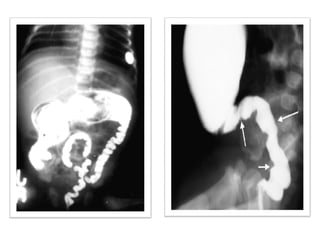

1. Plain x-rays of the abdomen :Erect & supine

2. Contrast enema

– contrast enema should be done without preparation

of bowel

– Shows narrow distal segment,

– funnel-shaped dilatation at level of transition zone

with marked dilatation of the proximal colon.

24-hrs delayed films

(child with psychogenic stool holding)

Investigations Radiology 1.Plain x-rays of the abdomen :Erect & supine 2. Contrast enema – contrast enema should be done without preparation of bowel – Shows narrow distal segment, – funnel-shaped dilatation at level of transition zone with marked dilatation of the proximal colon. 24-hrs delayed films (child with psychogenic stool holding)